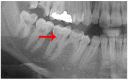

Background: This study sought to determine the prevalence of carotid artery calcifications (CACs) and pulp stones detected on panoramic radiographs (PRs) and ascertain their correlation.

Methods: A total of 2013 digital PRs were retrospectively retrieved and thoroughly examined to determine the prevalence of CACs and pulp stones, their correlation with patient age and gender, and the relationship between the presence of pulps stones and radiographically detectable CACs.

Results: The prevalence of CACs on PRs was 2.0%; the prevalence of pulp stones was 4.6%. There was no statistical relationship between pulp stones and CACs (p = 0.714). Older patients exhibited a significantly higher prevalence of CACs than younger patients (p < 0.001); pulp stones were statistically more prevalent in younger patients than older patients (p = 0.001). There were no significant differences between male and females in terms of the prevalence of either CACs or pulp stones (p = 0.087 and p = 0.278, respectively).

Conclusions: Dentists should be trained to detect CACs on PRs belonging to patients older than 40 to exclude the presence of CACs. Moreover, pulp stones do not function as a diagnostic marker for CACs.